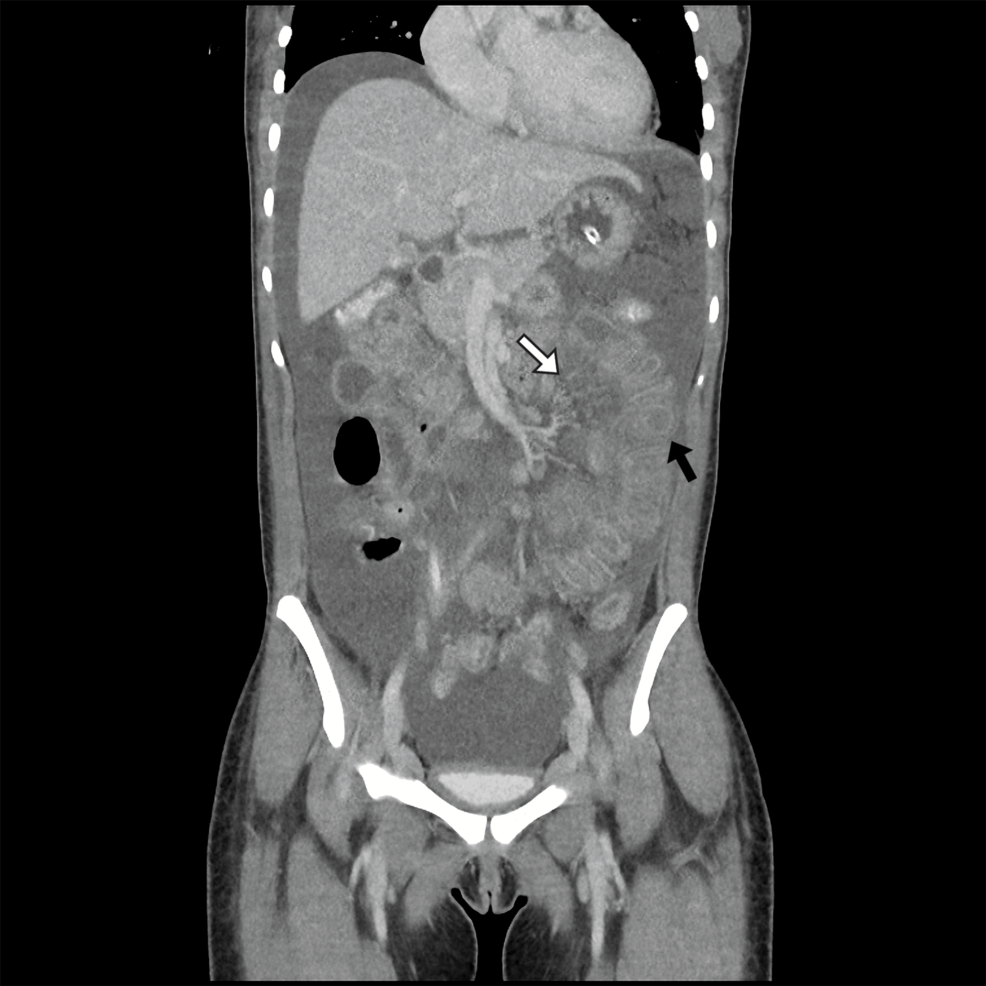

Abdominal CT with contrast Bowel wall thickening (>3 mm), “target” or “halo” sign, mesenteric edema, ascites Sensitivity ≈ 80 %; specificity ≈ 70 % [3].

Imaging Hallmarks

• Segmental bowel wall thickening – often in the jejunum/ileum.

• “Double‑halo” sign – inner mucosal hyperenhancement flanked by submucosal edema.

• Mesenteric fat stranding and fluid‑filled peritoneal cavity.

• Absence of pneumoperitoneum unless perforation has occurred.

• Imaging: Contrast CT revealed jejunal wall thickening (4 mm) with “halo sign” and moderate ascites.

• Management: Received IV methylprednisolone 1 g/day ×3, followed by oral prednisone 60 mg/day and cyclophosphamide IV (500 mg/m²).Symptoms resolved within 48 hours; repeat CT at day 7 showed normalized bowel wall.